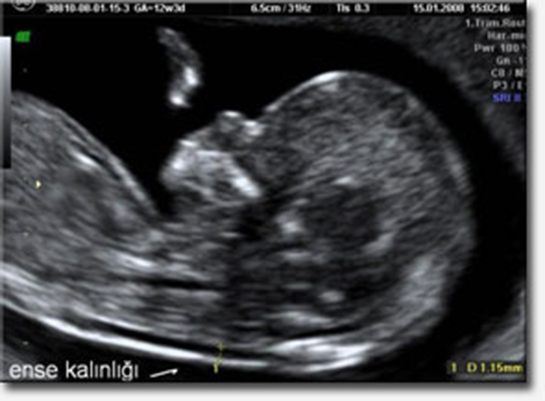

Bebeğinizin ense kalınlığını ölçmek, genellikle 11-14. haftalar arasında yapılan bir ultrason taraması ile gerçekleştirilir. Bu ölçüm, özellikle Down sendromu ve bazı kromozom anomalileri için risk belirlemede önemli bir göstergedir. 35 yaş ve üzeri annelerin bu testin sonuçlarına daha dikkat etmesi gerektiği doğru; çünkü yaş ilerledikçe risk oranı artmaktadır.

Normal ense kalınlığı sınırları genellikle 2.0 mm ile 3.5 mm arasında kabul edilir. Eğer ölçüm bu aralığın üzerindeyse, ek testler veya değerlendirmeler gerekebilir. Bu süreçte, uzman bir doktorun ölçümü yapması ve sonuçları yorumlaması oldukça önemlidir. Çünkü bu testin doğru bir şekilde yorumlanması, bebeğinizin ve sizin sağlığınız açısından kritik bir rol oynamaktadır.